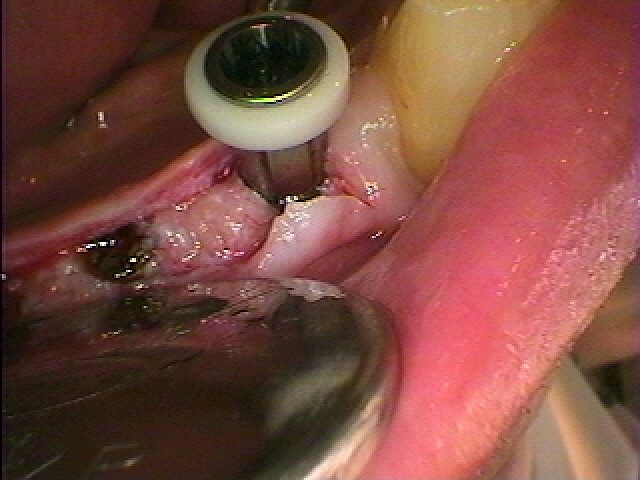

インプラントを埋入しています